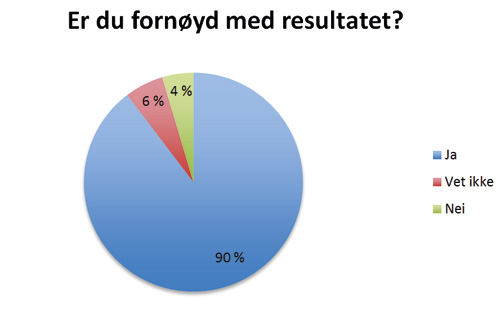

Formålet med denne studien var å vurdere resultater og komplikasjoner etter lukket fremføring av palatinalt retinerte hjørnetenner, samt å se på pasientenes subjektive opplevelse av behandlingen. Studien viser at 90 % av pasientene som responderte på tilsendt spørreskjema var fornøyde med resultatet. At de var fornøyde så ut til å være uavhengig om de opplevde peroperative- eller postoperative smerter. Heller ikke lang behandlingstid så ut til å redusere andelen fornøyde pasienter. Informasjon om endelig behandlingsresultat ble innhentet fra henvisende kjeveortopeder for 54 av pasientene. 52 av disse pasientene oppnådde vellykket fremføring av retinert tann. I de to tilfellene der resultatet ikke ble vellykket, ble tannen fjernet. Studien har i tillegg vist at frekvensen av komplikasjoner er lav etter behandling.

Er du fornøyd med resultatet?

En oversikt over antall forespurte og antall responderende pasienter sees i Tabell 1. Totalt 85 pasienter som samtykket til å delta i studien kunne identifiseres. For disse var det aktuelt å innhente journalopplysninger fra fakultetet og henvisende kjeveortoped. Hvordan pasientene opplevde operasjonen og behandlingen etterpå er presentert i Figur 2 - 6.

Figur 5. Er du fornøyd med resultatet?

Den subjektive opplevelsen til pasientene etter behandling av palatinalt retinerte hjørnetenner ved lukket fremføring ble vurdert ut fra svarene fra spørreskjemaet som ble sendt til den enkelte pasient. Vi har ikke funnet noen tidligere studier hvor spørreskjema er benyttet i evaluering av denne type behandling. 90 % av pasientene var fornøyde med resultatet etter behandling. Vår studie viser også at pasientene stort sett er fornøyd uavhengig om pasienten har opplevd smerte under eller etter operasjonen. 20 % av pasientene som oppga at det var svært smertefullt under operasjonen oppga at de ikke var fornøyd med resultatet mot kun 4 % av dem som oppga noe smerter under operasjon. Blant de pasientene som synes at hele prosessen med å få dratt frem hjørnetann var veldig ubehagelig, er det overvekt av pasienter som er fornøyd med resultatet. At 39 av 47 pasientene var fornøyde selv om de svarte at de synes det tok lang tid, gjør at man kan anta at lang behandlingsperiode heller ikke er avgjørende for om pasienten blir fornøyd.

Studien viser at pasienter som har gjennomgått behandling av palatinalt retinerte hjørnetenner ved lukket fremføring med feste av sleper er fornøyde med resultatet. At de er fornøyd med resultatet er stort sett uavhengig av om de har opplevd smerter under eller etter operasjon. I tillegg ser det ut til at de fleste pasientene som synes behandlingsperioden er lang, likevel er fornøyde med resultatet. Også blant pasientene som syntes hele prosessen med å få fremført en tann var ubehagelig er en overvekt av pasientene fornøyde.